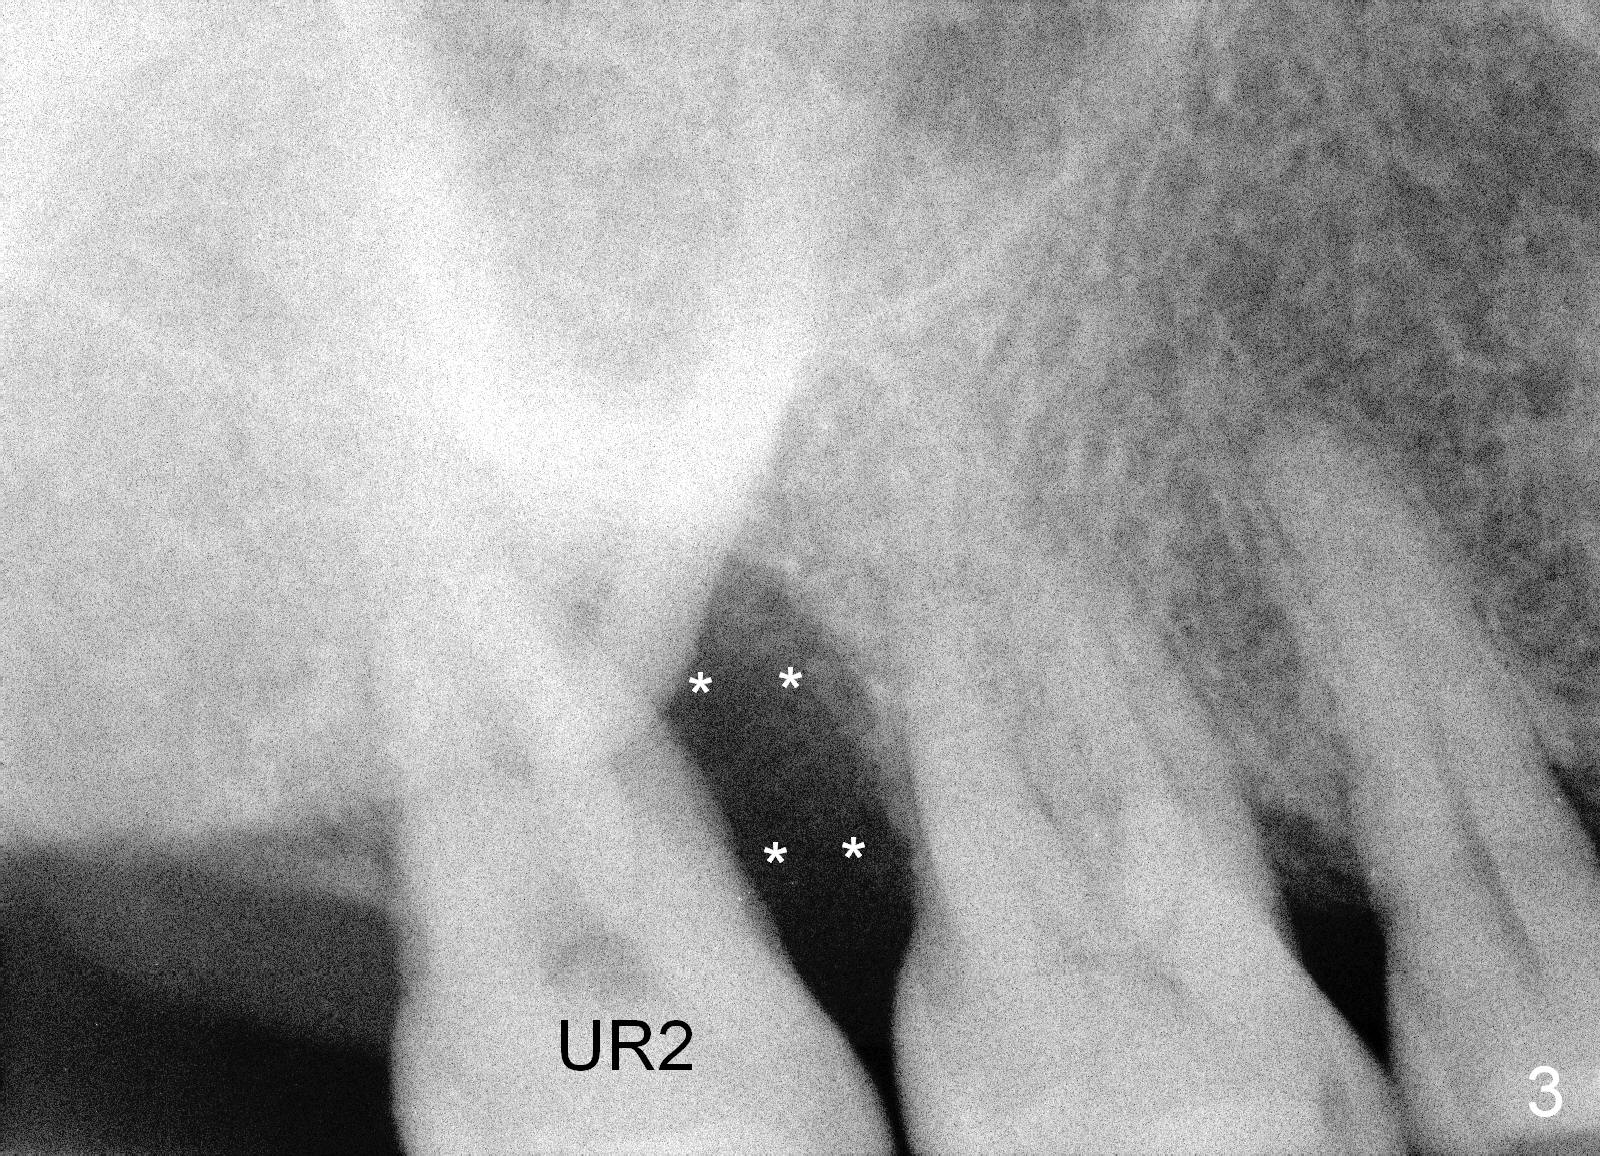

A 49-year-old lady is scared of dentistry. She presented with chronic periodontitis 7 years ago. The lower right 2nd molar had been missing (Fig.1 LR2), while the upper right 2nd molar shifted distally (arrow). Her chief complaint was mobility of #15 (Fig.2,4 UL2 with severe bone loss (*)). The tooth was extracted with expectation of return for implant placement in 6-8 weeks.

When she returns 7 years later, the tooth #2 has perio abscess with severe bone loss (Fig.3). She refuses to take antibiotic for infection control, but agrees to have immediate implant for #2 because of 1-staged surgery (Fig.5 I: 8x17 mm; A: abutment; P: bone powder (graft)). She is aware of delayed implants at the sites of #15 and 31 later. The bone height at the site of #15 reduces from 12 mm (Fig.4) to 7 mm (Fig.6) in 7 years.